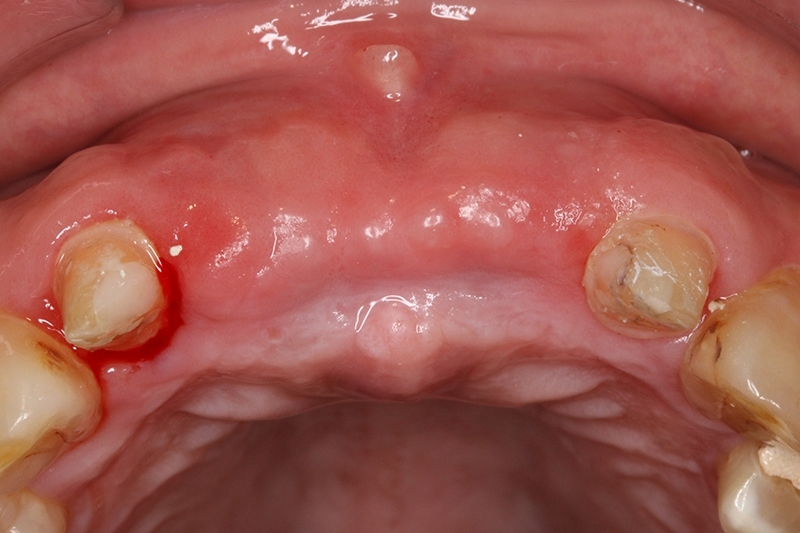

牙周治療前病患抱怨有膿在舊有的門牙植牙周邊,容易流血

經過牙周治療後,控制發炎,可見牙齦的狀況變得更健康了!

接續牙周治療完成後的療程,上排門牙植牙的問題處理,長期不斷的發炎化膿流血,除了造成周圍組織發炎與牙齦腫脹,同時造成齒槽骨被細菌破壞與吸收,根本解決的方式是建議移除感染與位置不佳的植體,先進行植牙移除手術+齒槽骨保存術,先使用膠原蛋白促進軟組織癒合,加快癒合的速度。

可見植體移除後骨缺損範圍大